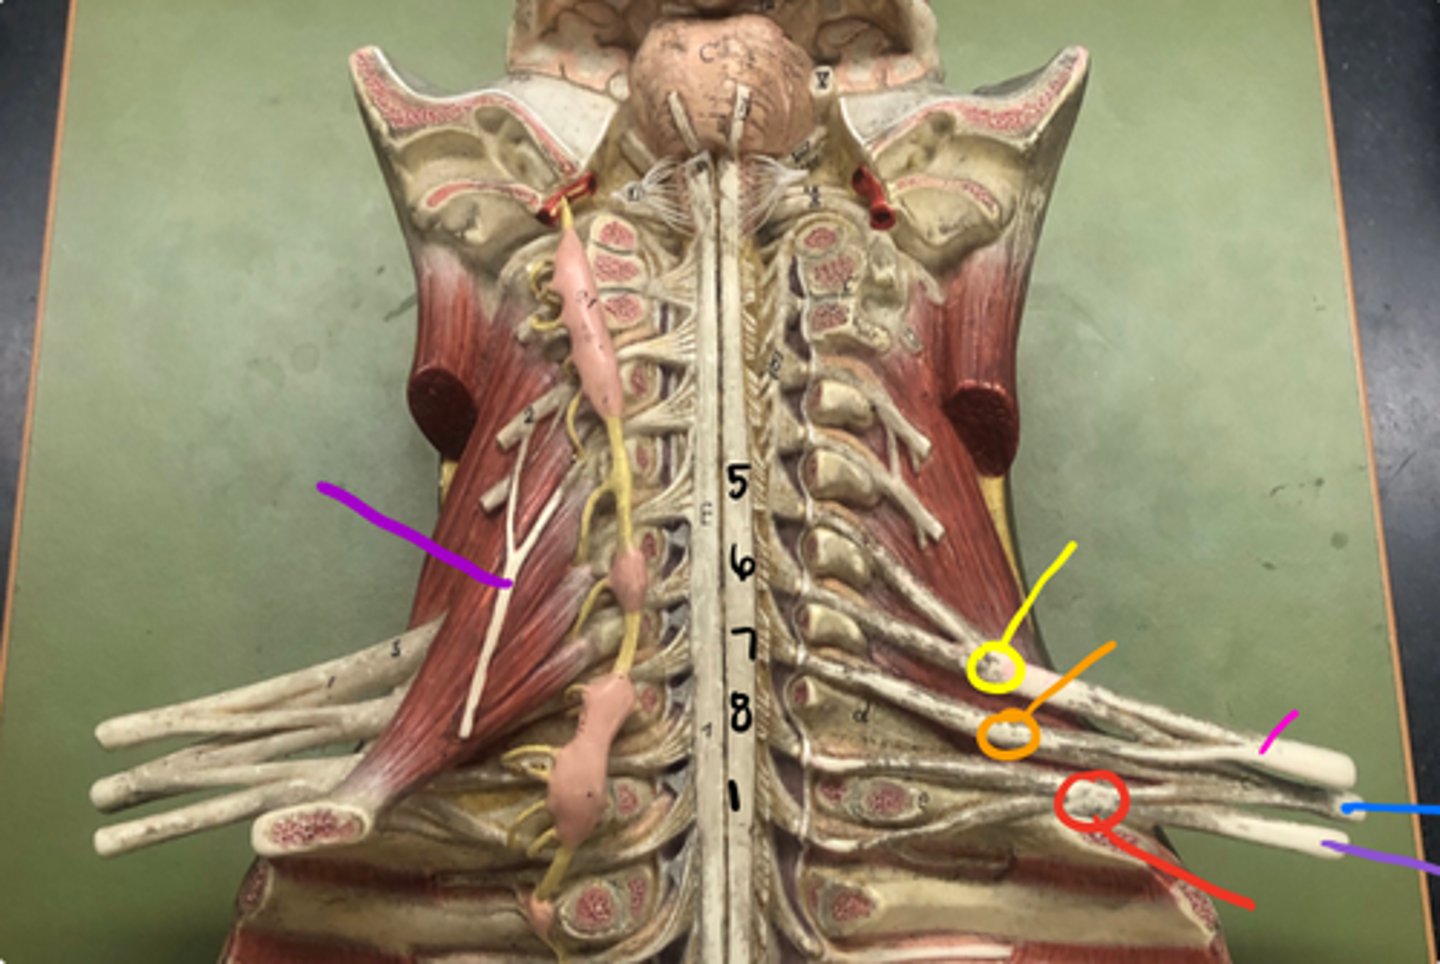

superior trunk

yellow

middle trunk

orange

inferior trunk

red

lateral cord

pink

medial cord

purple

posterior cord

blue

musculocutaneous nerve

median nerve

ulnar nerve

axillary nerve

dives deep near teres major

radial nerve

suprascapular nerve

Branches off the superior trunk

Seen on cadavers or picture

Subscapular nerve